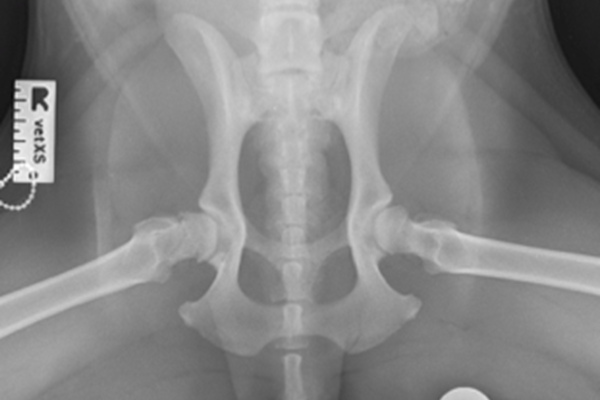

As a puppy, labrador retriever Bruce was always to run about and play. But Bruce's owner, Julie a registered head veterinary nurse from Warrington knew from an early age that Bruce had issues with hind legs. "Bruce always had 'clicky' hips and I was suspicious that there was a problem from when he was young puppy'. Bruce was first x-rayed at 6 months of age and Julie's vet, Dr. Iain Mottram from Warrington Vets4Pets noticed the hip abnormalities straight away. "Bruce's hip joints had not developed properly and the result was that the joints would 'slip' in and out of position - this condition is very painful" Dr. Mottram explains.

Bruce had further x-rays taken under anaesthetic so that his pelvis and femur could be very accurately measured for the implants that would be needed.